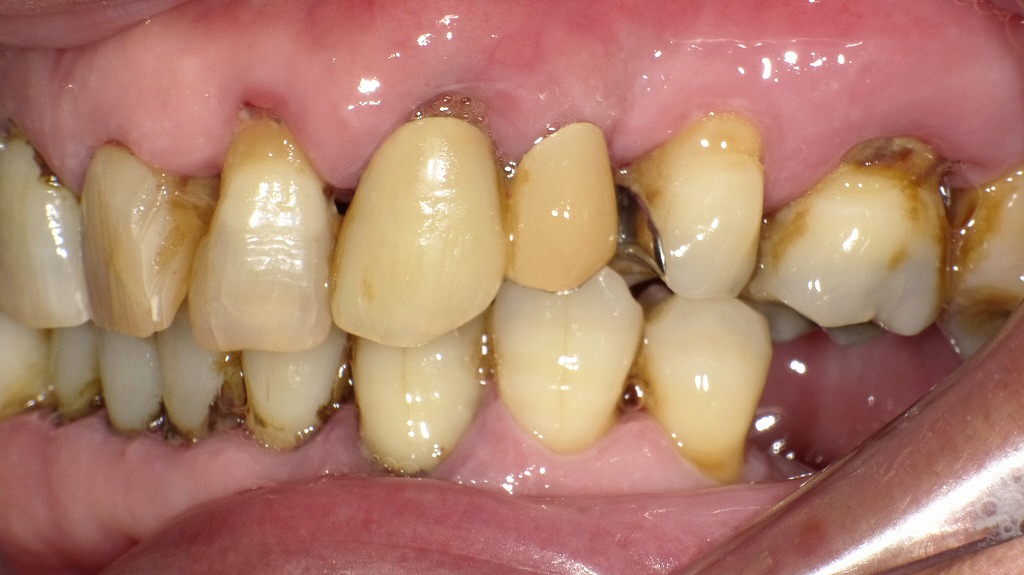

■ 歯周病はキスでうつる? 歯ぐきの状態から見える感染リスク

この口腔内写真では、複数の歯に以下のような特徴がみられます。

① 歯頚部(歯と歯ぐきの境目)に大量のプラーク(歯垢)

- 黄白色のベタついた付着物が多数の歯の歯頚部に見られます。

- プラークは細菌の塊で、歯肉炎・歯周炎の主原因になります。

② 黒褐色の歯石(特に下顎前歯部・上顎臼歯部近心)

- 歯の側面に黒色〜濃褐色の固まった沈着物が見られます。

- これは縁下歯石と呼ばれることが多く、タバコのヤニや血液成分と反応して黒く変色します。

- ブラッシングでは取れず、専門的スケーリング/ルートプレーニングが必要です。

③ 歯肉の発赤・腫脹(歯肉炎)

- 歯肉が赤く腫れ、境界が丸みを帯びています。

- プラーク刺激により炎症が起きている典型所見です。

- 出血しやすい状態です。

④ 歯周病の進行が疑われる所見

- 歯石の量が多く、歯肉退縮や歯根露出が局所的に認められます。

- 一部歯が前後方向に傾斜・移動しており、歯周組織の支持力低下が疑われます。

- 歯の動揺が起きています。

⑤ 咬耗・変色・古い補綴物の不調和

- 複数歯で咬耗(すり減り)があり、茶色いステインが付着。

- 古い被せ物と天然歯の境目にもプラークがたまりやすい状態となっています。

■ 総合的な評価

この症例は、中等度〜重度の歯周病が進行した状態を示しています。

- プラークと歯石の大量付着

- 歯肉の炎症所見

- 歯の変位(動揺が疑われる)

- 歯頚部の歯周組織破壊

これらはすべて歯周病の典型的なサインです。

■ 歯科的に考えられる必要な処置

- 徹底したスケーリング・ルートプレーニング(縁上・縁下歯石の除去)

- 歯周精密検査(歯周ポケット測定・動揺度・X線)

- 歯周基本治療(ブラッシング指導を含む)

- 必要に応じて歯周外科治療

- 補綴治療の見直し